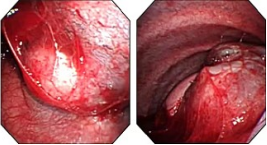

近年来,贵州航天医院各科室紧跟医学前沿,不断强技术、补短板,大力开展新技术、新项目,完成了许多高精尖、高难度、本地区“首例”的技术,填补了医院医疗技术空白,满足了群众日益增长的医疗需求。 贵州航天医院呼吸与危重症医学科是贵州省内呼吸疾病治疗规模最大,诊疗项目最全的呼吸疾病品牌科室,呼吸介入技术达到了全国先进水平,在贵州省内处于领先的地位。 本期,我们将为大家带来呼吸与危重症医学科特色技术——内科胸腔镜技术诊断和治疗胸腔疾病。 案例分享 患者苟某某,因劳累、气促,不明原因胸腔积液在某县一医院采取反复抽水等治疗手段效果不佳,当地医院考虑到患者年龄大(77岁),基础疾病较多,病情复杂,结合当地诊疗水平能力情况,建议转到上一级医院诊治,通过我院与该院建立的呼吸专科联盟绿色通道转入了我院。 患者入院后,呼吸与危重症医学科第一时间复查胸部CT,提示:右肺中叶、左肺感染,纤维化灶,左侧中量胸腔积液,右后侧胸膜轻度增厚,心包少量积液;并完善心电图、血常规、凝血功能、生化指标等术前检查。经科室专家团队集体讨论,得出患者左侧胸腔积液可能原因:结核?恶性?其他?冠心病、心功能不全、高血压病3级(高危组)、陈旧性肺结核复发?肺部感染;为进一步明确诊断,在充分评估、做好术前准备及应急预案、与患者及家属沟通的情况下,决定为患者进行内科胸腔镜检查术。 科室在患者入院第3天便实施了内科胸腔镜检查术,经检查取活检,病理不排除胸膜间皮瘤,送遵义医科大学附属医院病理会诊后诊断:胸膜间皮瘤。明确诊断后,科室专家团队为患者制定了个体化的治疗方案,患者病情很快得到有效控制,最终满意出院。半年后,医院通过电话回访,患者病情稳定,生活质量明显改善。 什么是内科胸腔镜 内科胸腔镜(medical thoracoscopy,MT)是一项微创诊断和治疗胸腔疾病的重要技术。主要应用于无创方法不能确诊的胸腔积液和胸膜疾病,通过局部麻醉后在胸壁做一个小切口,插入胸腔镜,直接观察胸膜、肺表面、纵隔等部位的病变情况,可进行活检、粘连松解及胸膜固定等操作。具有创伤小、恢复快、诊断准确性高等优点。 内科胸腔镜原理 内科胸腔镜是一项利用现代光学技术和成像技术的侵入性操作技术,应用电子支气管镜、硬质或软硬结合(半硬)的胸腔镜的一种电子内窥镜,末端装有连接着显示屏的微型摄像头。通过胸壁1-2cm左右的小切口,将内科胸腔镜及专用器械(戳卡套管)通过小切口进入胸腔,微型摄像头将胸腔内的情况投射到显示屏幕上,医生可以通过镜头全面、直观地观察患者胸腔内情况,了解胸膜病变确切位置和形态改变,还可对胸膜上的病变进行活检及治疗的操作技术,安全、微创、几乎无痛地“揭秘”不明原因的胸腔积液。 内科胸腔镜技术优势 (一)安全性高:仅需局部浸润麻醉,并发症发生率相对较低,对患者的身体条件要求较低。 (二)操作简便:操作时间短,痛苦少,患者耐受好。 (三)微创性:切口小,对患者身体损伤小,术后疼痛轻,恢复快。 (四)高分辨率成像:清晰显示胸腔内细微病变,提高诊断准确性。 (五)可直视操作:直接观察病变,进行精准活检和治疗。 (六)适用范围广:可用于不明原因胸腔积液、胸膜疾病、肺部疾病等的诊断和治疗。 (七)费用低:与外科胸腔镜比较费用低廉。 内科胸腔镜技术是贵州航天医院呼吸专科和呼吸介入诊疗优势的一部分,在2016年率先开展了内科胸腔镜技术,年手术量约100余例,已建立了快速、精准、规范、有效的一体化诊疗服务体系。目前呼吸与危重症医学科内科胸腔镜技术广泛应用于不明原因胸腔积液、气胸、脓胸的诊断和肺癌、弥漫性恶性胸膜间皮瘤等的分期,恶性或复发性胸腔积液、早期脓胸、自发性顽固性气胸的治疗。 镜下常见表现:单发或多发结节、灰白色弥漫性粟粒样结节、胸膜充血、水肿、胸膜增厚及纤维分隔或粘连带形成。 诊断方面: 胸腔积液的病因诊断。内科胸腔镜对恶性胸腔积液的诊断率可高达90%以上,胸腔镜对结核性病变诊断率极高,几乎达到96%以上。 腺 癌 恶性淋巴瘤 软骨肉瘤胸膜转移 滑膜肉瘤胸膜转移 结核性胸膜炎 治疗方面: 脓胸 肺大泡 贵州航天医院 呼吸与危重症医学科学科带头人 廖江荣 国务院政府特殊津贴专家 二级教授 主任医师 贵州航天医院副院长 国家级学术任职: 第二届中国医药教育协会介入微创专业委员会呼吸分会副主任委员 中国抗癌协会肿瘤微创治疗专业委员会常务委员 中国防痨协会结核病转化医学专业分会常务委员 第一届中国人体健康科技促进会呼吸介入专委会常务委员 中国医疗保健国际交流促进会结核病学分会第三届委员会常务委员 中国抗癌协会肿瘤微创治疗专业委员会粒子治疗学组第四届委员会委员 中华医学会结核临床专业委员会内镜介入委员 中华医学会放射学分会第十五届委员会介入学组呼吸系统介入专业委员会委员 北京健康促进会中青年专家委员会胸部疾病精准活检分委会副主任委员 中国医师协会介入医师分会第二届委员会肿瘤消融专业委员会委员 中国结核病防治综合质量控制专家指导委员会委员 亚洲冷冻治疗学会常务委员 世界内镜医师协会呼吸内镜协会常务理事 内镜临床诊疗质量评价专家委员会委员 “西部呼吸介入联盟”副理事长 专业擅长: 贵州航天医院 呼吸与危重症医学科简介 贵州航天医院呼吸与危重症医学科以呼吸危重症和介入呼吸病学为强力推手,以肺部感染性疾病及肺癌、肺小结节的早期精准诊疗、慢性呼吸疾病康复治疗为特色,以人才团队建设为核心的科室发展模式,现已成为省内呼吸疾病治疗规模最大,诊疗项目最全的呼吸疾病品牌科室。是贵州省医学重点学科、临床医学重点专科建设单位,遵义市首批呼吸重点学科、重点专科建设单位。是国家卫健委能力建设和继续教育肿瘤微创介入建设中心、贵州省县级医院微创介入培训中心、遵义市呼吸疾病临床医学中心。是国家呼吸医疗质量控制与管理哨点医院、遵义市呼吸内科专业医疗质量控制中心。是中国医药教育协会介入微创呼吸分会呼吸介入技术培训中心单位;国家卫健委海医会呼吸分会ROSE专委会“诊断性介入肺脏病学快速现场评价”培训基地;中国肺癌防治联盟“贵州航天医院肺结节诊治”分中心,中国人体健康科技促进会呼吸介入技术培训基地,贵州省中西医结合会呼吸学分会呼吸介入专委会主委单位。 基本情况 平均每年开展气管镜诊疗约4000例,经皮肺穿刺介入诊疗近千例,开展的项目包括经支气管镜(软、硬)下冷冻、氩气刀、高频电刀、球囊扩张、支架置入、超声内镜诊疗等气道介入诊疗技术,经皮肺穿刺活检及肿瘤消融术(微波、冷冻)、ROSE技术、内科胸腔镜诊疗及经血管介入诊疗技术,且多项呼吸介入诊疗技术在省内处于领先水平。 诊疗范围 航天医院呼吸专科擅长:致力于呼吸系统感染性、疑难性疾病的介入快速精准诊疗;肺癌与肺小结节早期精准诊疗水平项目提升。擅长于呼吸系统(肺)疑难病的诊断及危重病的救治,尤其在肺癌、肺小结节的早期诊断;肺癌综合靶向治疗;肺结核综合诊疗;肺部疾病的介入诊疗在省内处于前沿水平。 咨询热线 (一)呼吸与危重症医学科一病区 医生办公室:27677317 护士站:28614217 (二)呼吸与危重症医学科二病区 医生办公室:28691274 护士站:28690442 (三)呼吸与危重症医学科三病区 医生办公室:28692417 护士站:28690461 (四)呼吸与危重症医学科四病区 医生办公室:28616402、27677582 护士站:28614987、27677862